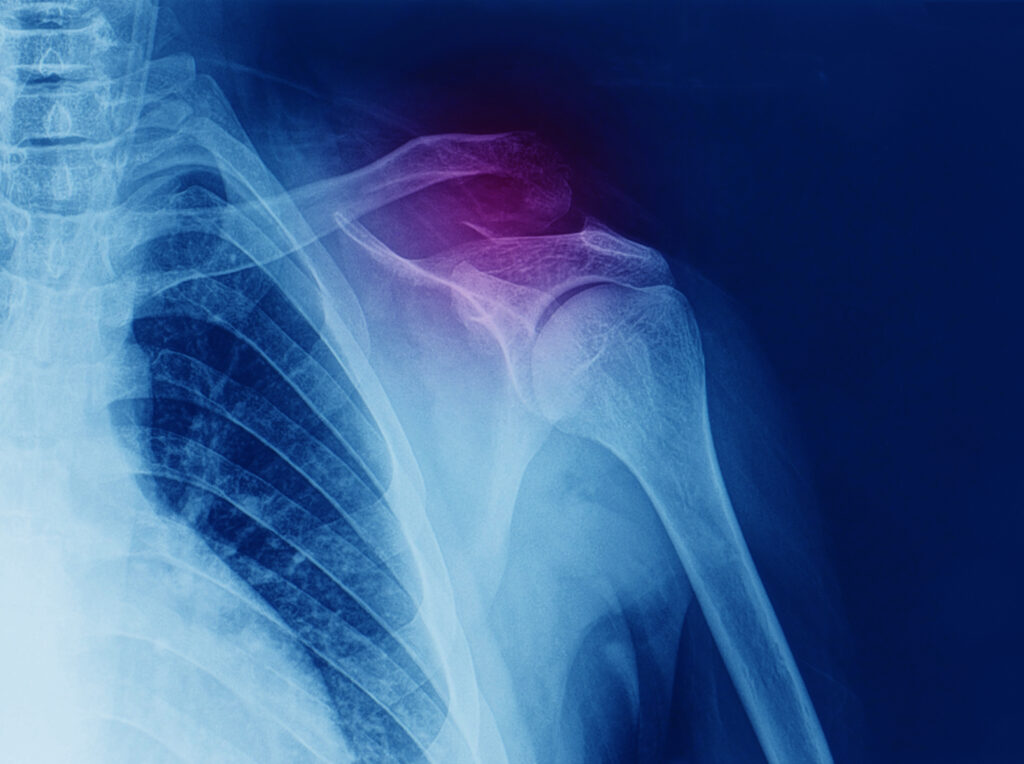

پارگی کاف روتاتور

پارگی کاف روتاتور پارگی کاف روتاتور چیست؟آسیب دیدن گروهی از عضلات و تاندون‌های شانه است. پارگی کاف روتاتور عضلاتی را